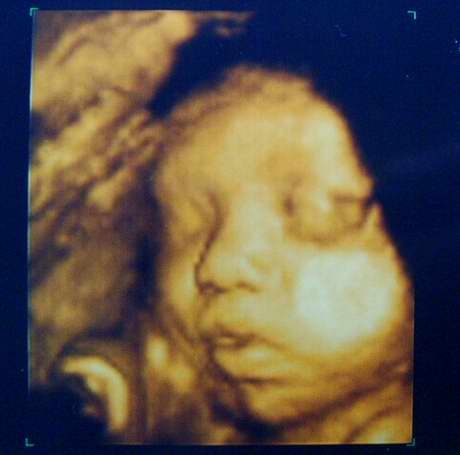

[第二次4D超音波-31w3d]

今天是照第二次4D超音波的日子,

不過因為老大要值班,所以只有我一個人去照....

沒想到小菜包卻意外的賞臉,今天把臉轉過來了....

我家小菜包可愛的臉~.

*偷偷睜開眼睛,護士講的時候我還沒發現哩,右眼有偷偷瞇開。

*才誇獎他今天好乖,沒想到馬上手就來了,還把手指頭塞進嘴裡。

手指頭還滿修長的說...XD。

*快結束時,小菜包開始打嗝,側面可以看到微微的抖動好幾下。

今天我的寶貝小菜包真的很乖哩....^^